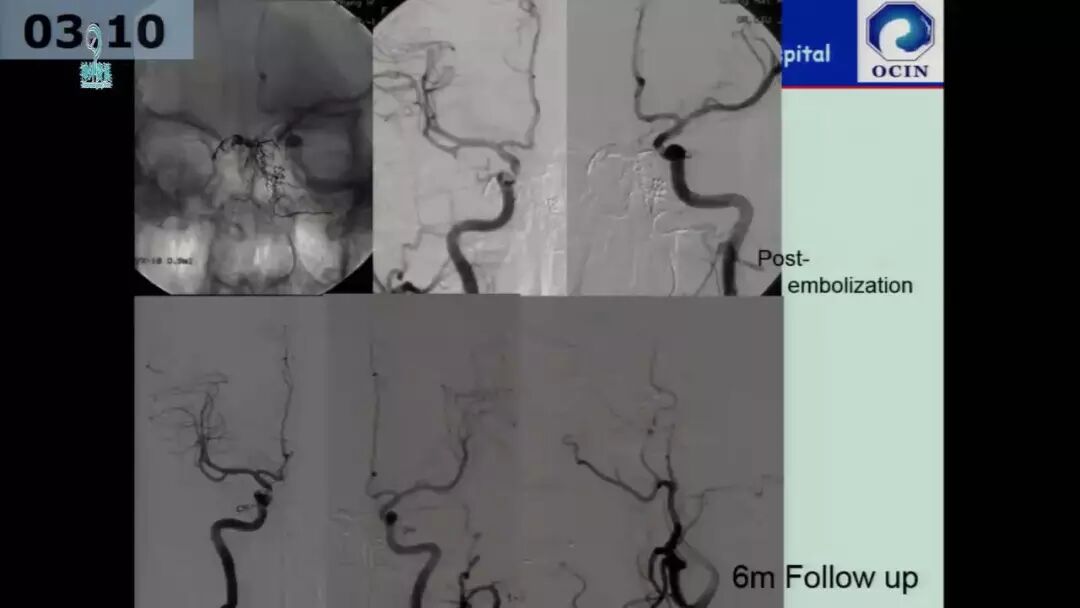

今天为大家分享的是由海军军医大学附属长海医院许奕教授在四川省医学会第十二次介入医学学术暨西南神经介入高峰会议上带来的“海绵窦区脑膜动静脉瘘的介入治疗”精彩讲课视频和PPT,欢迎观看!(内容未经讲者审核,不当之处请与我们联系)

许奕教授:海绵窦区脑膜动静脉瘘的介入治疗